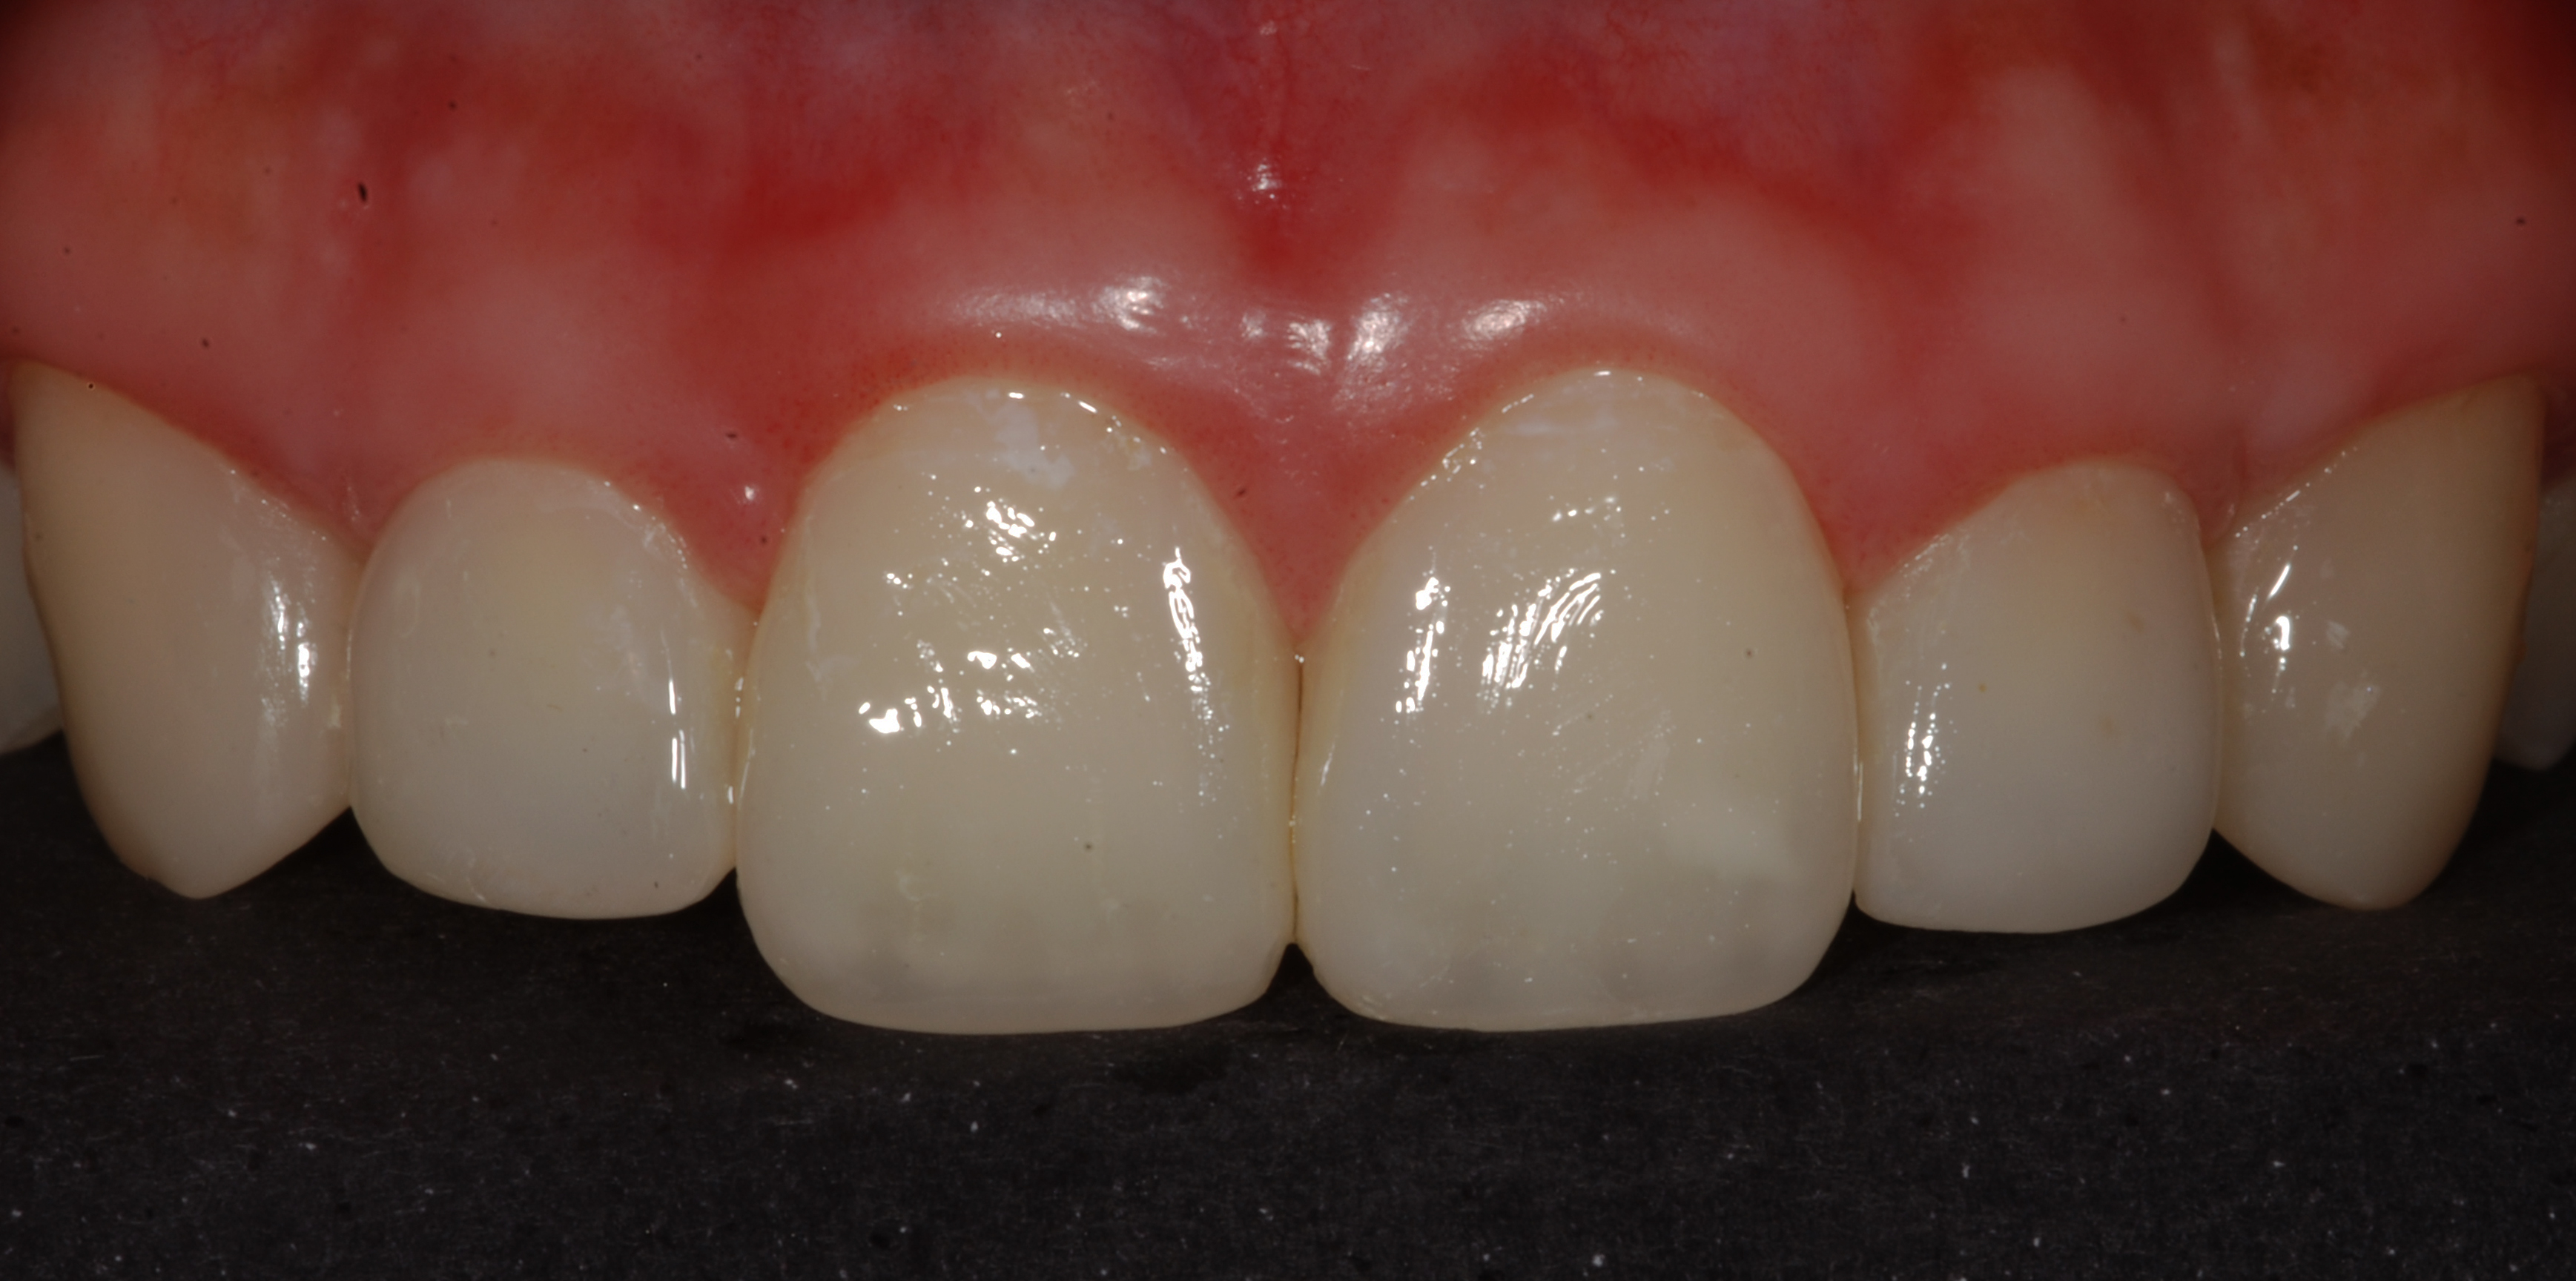

The presence of diastema, between anterior teeth, distorts a pleasing smile by concentrating the observer’s attention on the spaces. The patient’s needs and expectations must be considered in the process of treatment planning to ensure satisfaction with the treatment outcomes. There are many forms of therapy that can be used for diastema closure. A carefully developed diagnosis, which includes a determination of the causal elements and advanced treatment planning, allows the most appropriate treatment to be selected for each case. The aim of this paper is present a multidisciplinary approach as a solution to multiple diastemas in the anterior region using gingival tissue recontouring and direct adhesive restorations, with minimum wear of the dental structure, after the orthodontic intervention discussing the minimal intervention to obtain imperceptive and aesthetic final restoration. Thirty-six months after the treatment was carried out, the final aesthetic was maintained with all dental element details and gingival tissue harmony, without recurrence of periodontal pockets and the preservation of the tooth color and shape.